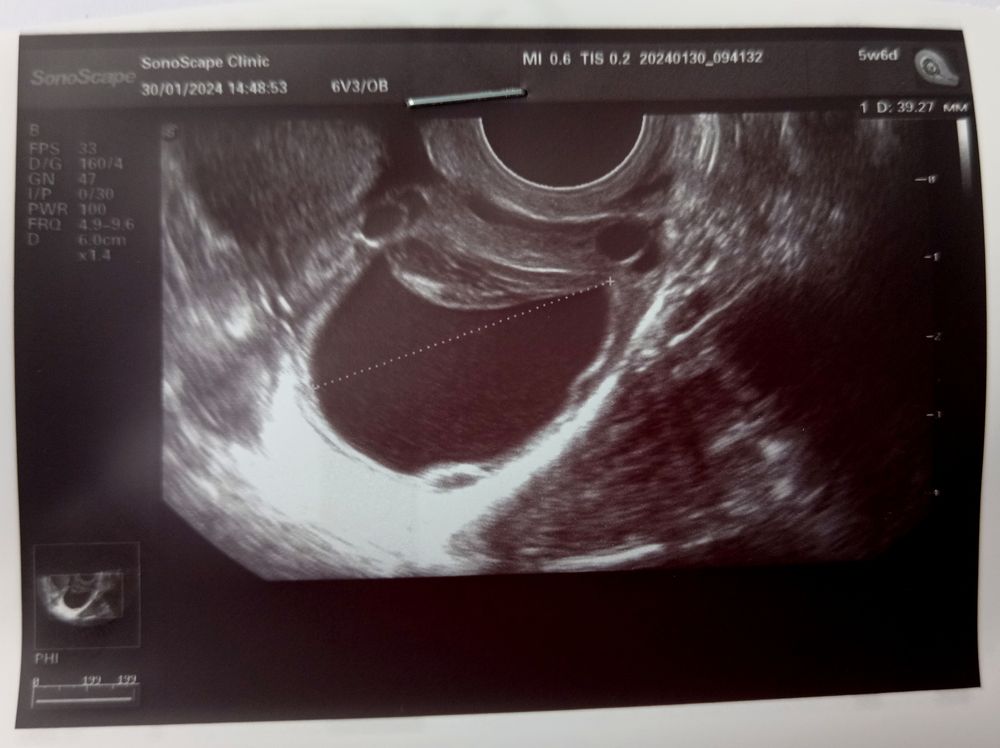

Дело такое... 42 дц и 7-9 дз. Сегодня была На УЗИ заключение: МФЯ и КЖТ😣. Фото прикрепляю 👇